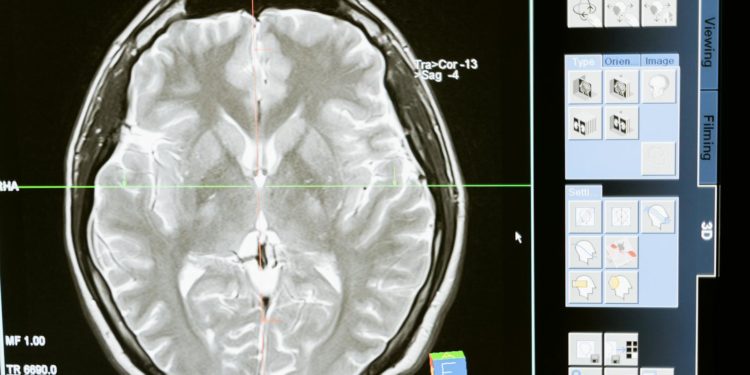

A l’aide de méthodes innovantes d’imagerie moléculaire in vivo réalisées par imagerie par émission de positons (TEP Scan), l’équipe toulousaine a pu observer pour la première fois les niveaux d’inflammation cérébrale des patients dans le coma et les comparer à ceux de personnes en bonne santé. Ces observations ont permis de mettre en exergue l’importance du rôle de l’inflammation cérébrale au cours du coma, en ouvrant ainsi un nouvel axe de recherche avec des retombées médicales potentiellement majeures sur les patients dans le coma.